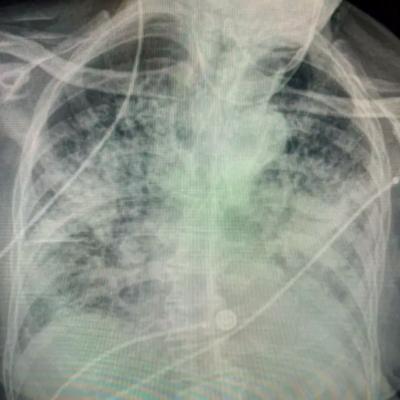

त्यांनी ट्विटरवर या आजाराचा प्रभाव दाखवण्यासाठी तीन एक्स रेजचा फोटो पोस्ट केला होता. त्यातील एक फोटो स्मोकर फुफ्फुसांचा होता, दुसरा एक्स रे कोरोनातून बाहेर आलेल्या एका रुग्णाच्या फुफ्फुसांचा होता. तिसरा एक्स रे निरोगी माणसाचा होता.

. तिन्ही फुफ्फुसांच्या एक्सरे मध्ये खूप फरक दिसून आला. स्मोकरची फुफ्फुसं खूप काळी होती. कोरोनावर मात केलेल्या रुग्णाची फुफ्फुसं पांढरी दिसत होती.

ही फुफ्फुसं खूप पांढरी दिसत होती. डॉक्टरांनी दिलेल्या माहितीनसार कोरोनामुळे फुफ्फुसांपर्यंत योग्य प्रमाणात हवा न पोहोचल्यामुळे फुफ्फुसं अशी दिसत होती.

यांनी सांगितले की, ''कोरोना पॉझिटिव्ह झाल्यानंतर तुमच्या फुफ्फुसांची स्थिती खूप खराब होऊ लागते. श्वास घेण्यासाठी त्रासाचा सामना करावा लागू शकतो. याशिवाय फुफ्फुसांच्या इतर समस्यांचा सामना करावा लागू शकतो.''